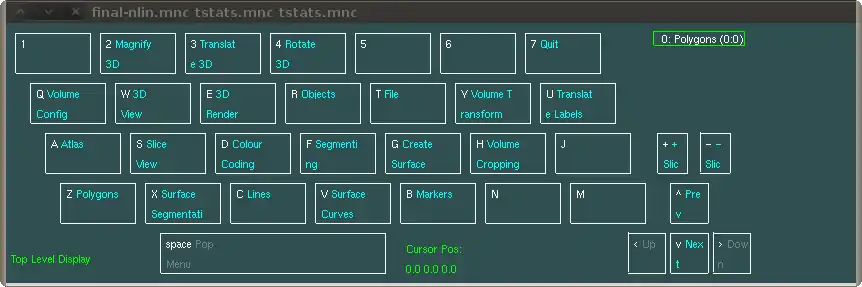

Display is a hugely versatile program, and perhaps is best explained by example. Its main purposes are segmenting, visualizing/overlaying several MINC files and visualization of 3D objects.

Overview of steps in Display:

- click "space Pop Menu" or press space bar to get to the main menu if you were not there already

- click "T File" or press "t"

- click "Y Load UserDef ColCo" or press "y"

- On the command line type: "/micehome/jlerch/luts/hotred" and press "enter"

Display has a control panel. You can click on the buttons with your mouse, or use the keys on the keyboard (e.g, clicking on "D Colour Coding" will do the same thing as pressing the "d" on your keyboard). When you click on "D Colour Coding" you get to a menu that allows you to change the colours to gray, hot metal, spectral... Try them out and see what they do. In our case, we want to use user defined colours, and so we will need to load those in. These are text files that indicate which colours belong to which points along the colour bar. See below for an example. If you went into the Colour Coding tab in Display, press the space bar or "space Pop Menu" to get back to the main menu. There go the "T File", and then to "Y Load UserDef ColCo". As soon as you pressed the latter, Display will become unresponsive because it is awaiting input from the command line. So go to the shell which started Display. If will say: